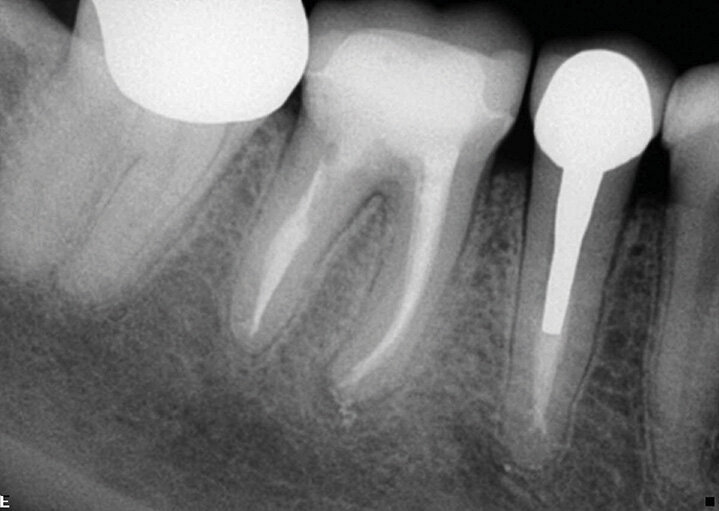

Slučaj 2 – Slika br. 4: Inicijalni periapikalni Rtg snimak

Slučaj 2 – Slika br. 5: Periapikalni kontrolni Rtg snimak odmah nakon tretmana

Slučaj 2 – Slika br. 6: Periapikalni kontrolni Rtg snimak nakon godinu dana od tretmana

Pacijent je upućen na retretman donjeg molara. Početni rendgenski snimak prikazuje metalni liveni kočić u distalnom kanalu, separiran instrument u jednom od mezijalnih kanala i radiolucenciju na apeksu. Pacijent je obavešten da ću morati da mu uklonim staru krunicu i metalni kočić da bih mogao da uradim enododntski retretman i to će mi omogućiti pristup kanalima korena da ih ponovo obradim i napunim. Alternativa je da bila da uradim mikrohirurgiju na mezijalnom korenu, ali za ovo bih morao da isečem dugačak deo korena da bih postigao hermetičko zatvaranje unutar kanala zbog zalomljene turpije i nedostajućeg dela kanala koji nije tretiran. Pacijent je prihvatio prvi izbor. Prvi koraci su bili sečenje krunice i njeno uklanjanje, zatim sam nastavio sa delikatnim sečenjem metalnog kočića kako bi ga uklonili deo po deo. Deo zuba u kojem je kočić sam vibrirao ultrazvukom i bezbedno ga skidao. Ovo mi je omogućilo pristup gutaperki ispod. Koristio sam isti redosled turpija, Traverse i Zenflex. U distalnom korenu sam uspeo da idem sve do radne dužine, u mezio-bukalnom takođe do kraja, u mezio-lingvalnom sam stao gde je bila separiran isntrument. Ovde sam počeo da koristim male K-file turpije veličina 06 08 10 i 15 da zaobiđem instrument, imao sam sreće da to uradim pa čak i da je izvadim iz unutrašnjosti zakrivljenosti, i napravljeno je potpuno čišćenje i oblikovanje, praćeno 3D obturacijom sa elements IC (Slika br. 4). Jednogodišnje praćenje (Slika br. 5) pokazuje odlično izlečenje.